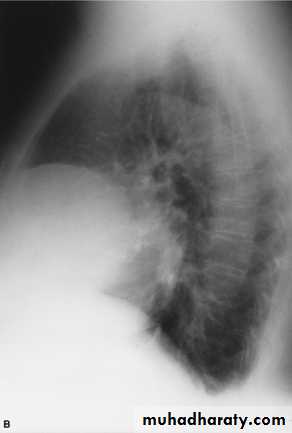

Pneumomediastinum.

Vertical dark (lucent) lines representing air within the mediastinum are usually seen at or above the level of the aortic arch.On the posteroanterior view (A), these can be seen extending up into the lower cervical soft tissues (arrows).

On the lateral view (B), dark linear air collections can be seen in front of and behind the trachea.